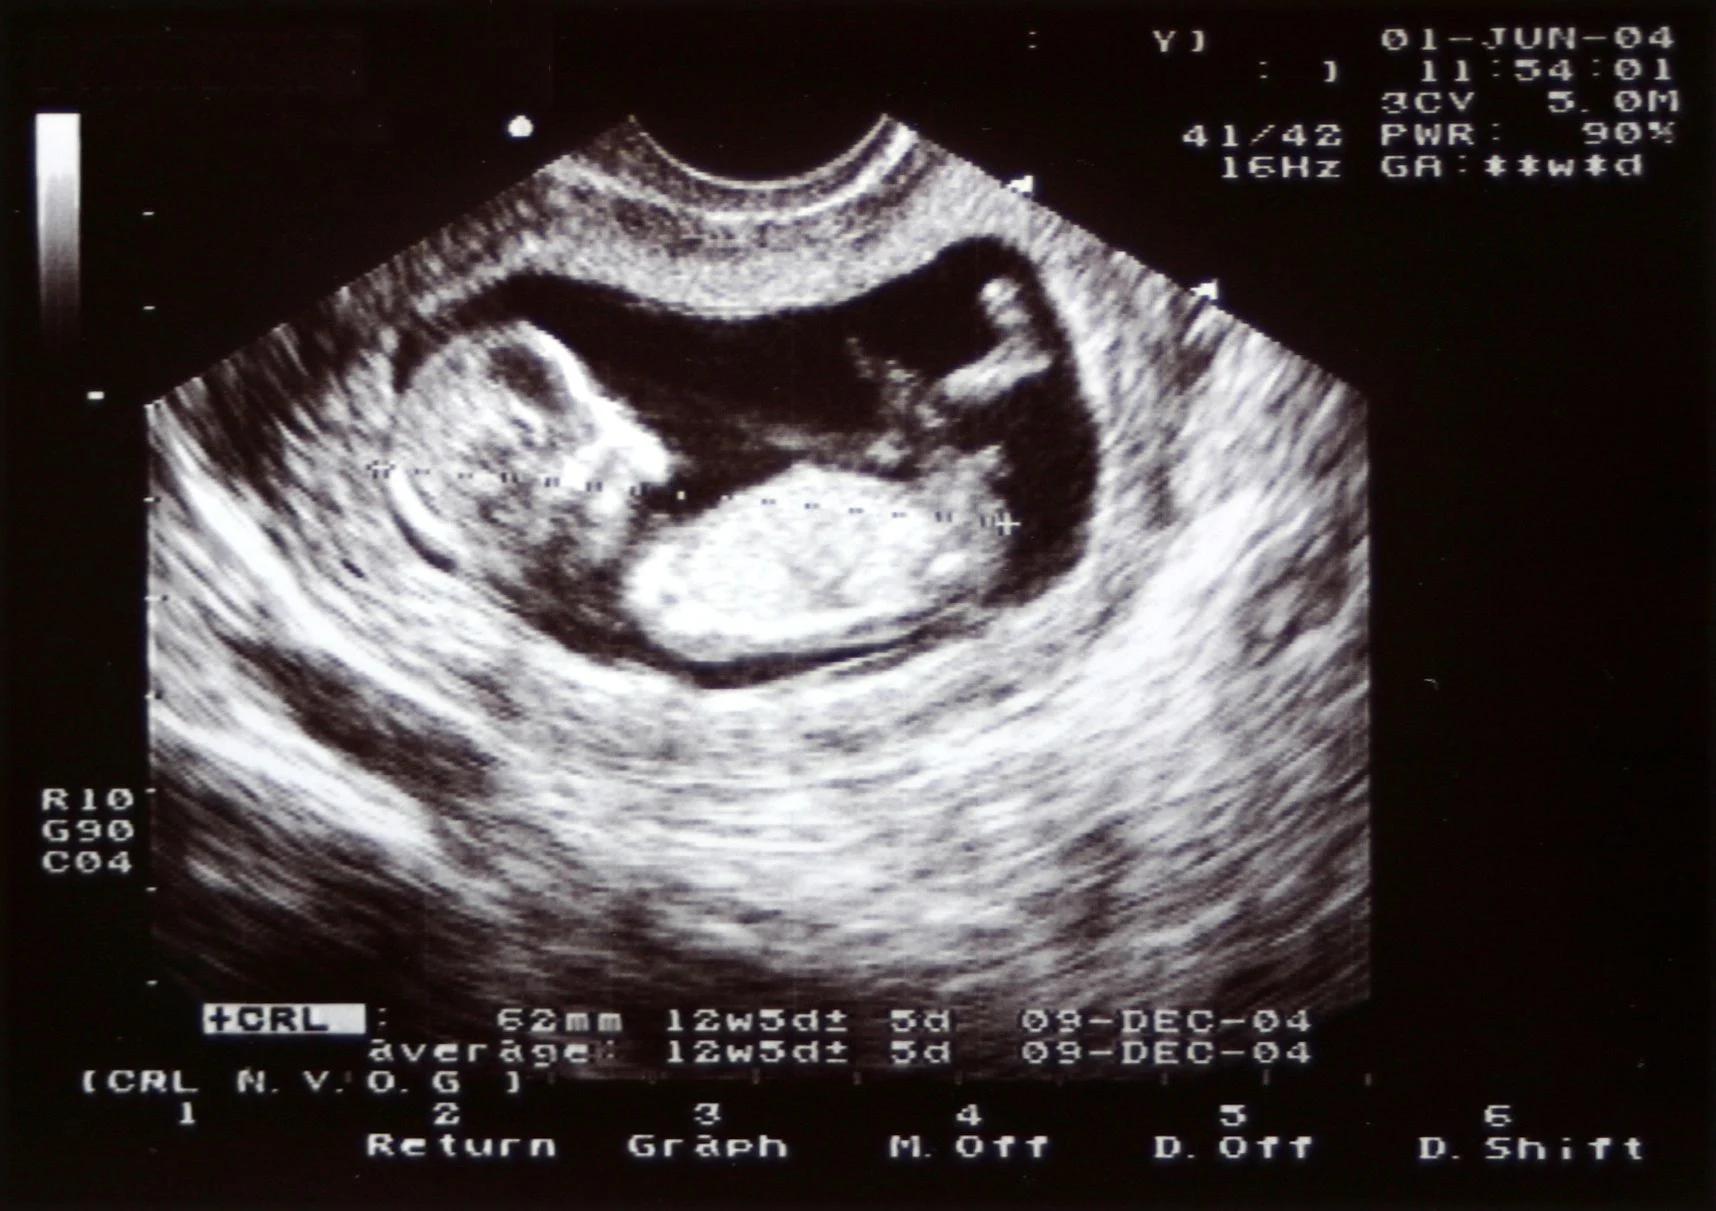

- Screening: In der 1bis 2Schwangerschaftswoche. Dieses Screening dient dazu, die Entwicklung des Kindes zu überprüfen, mögliche Fehlbildungen zu erkennen und die Lage der Plazenta zu beurteilen.